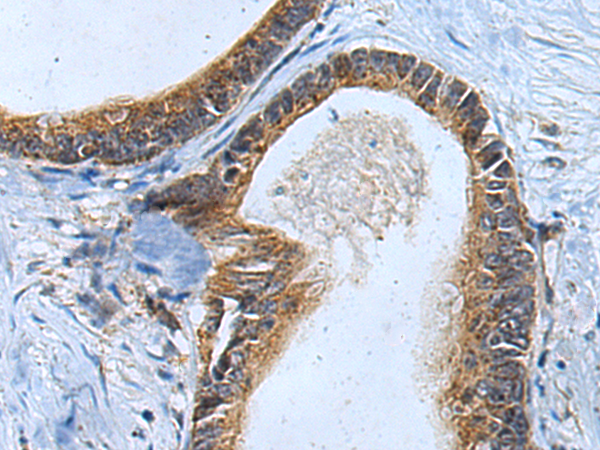

分类: 科研抗体货号: P09433别名: CPH应用: WB,IHC反应种属: Human, Mouse, Rat